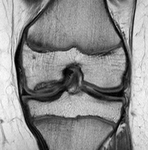

Magnetic resonance imaging (MRI) of knee demonstrating healing

From the collection of H. Chambers, MD